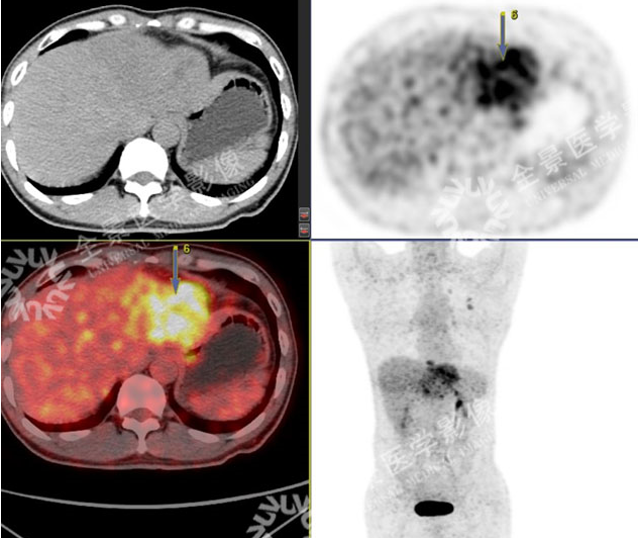

男性,57 岁,上腹疼痛 2 月余,加重 1 周。外院 CT:肝左叶占位。既往有乙肝病史多年。

SUVmax = 4.59

PET 示:腔静脉裂孔处结节 FDG 摄取增高;

CT 示:无明显异常密度影。

怀疑:腔静脉癌栓?后心膈角区淋巴结?

确诊:腔静脉癌栓